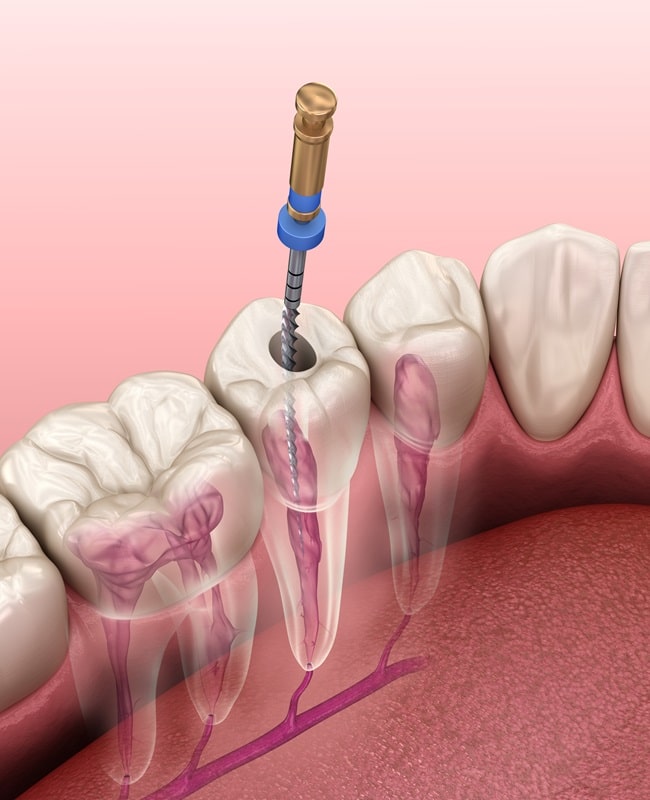

A root canal treatment is required when you have a tooth infection. The treatment allows us to remove the infected tissue inside the tooth, replace it with a substance called “gutta percha,” and close up the tooth, securing it with a dental restoration (usually a dental crown). These steps help save the tooth and prevent the spread of the infection.

Understanding Root Canal Treatments

Although the teeth are made up of hard tissue on the outside, there is an inner “pulp” inside the teeth, which is made up of soft tissue. This pulp is susceptible to infection when bacteria enter the tooth (usually through a cavity or hole in the tooth). When these infections occur, they can greatly affect the mouth, and if a root canal treatment is not performed in a timely manner, the tooth may need to be extracted. This is why it’s always best to see your dentist as soon as possible when you suspect you may have a tooth infection.